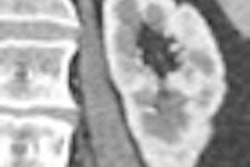

![]() |

| Most false positives were generated by small branches of sheetlike structures. Most false negatives resulted from thin haustral folds. |

| Results table shows the number of haustral folds, true positives (TP), and false positives (FP) (in each of 12 cases). Sensitivity was 81.7% with 6.9 false positives per case. |

In the previous study, published in 2000, Sato and colleagues proposed a sheet structure enhancement filter. The method succeeded in detecting haustral folds with a sensitivity of 76.3%, but it led to overdetection of haustral folds in areas of CT images that were sandwiched between colonic wall regions, Oda said of the study (IEEE Transactions on Visualization and Computer Graphics, April-June 2000, Vol. 6:2, pp. 160-180).

The present study, using an RSE enhancement filter, succeeded in detecting the ridges of the haustral folds with greater sensitivity than the previous study. However, further refinements will be needed to take full advantage of the data generated, Oda said.

Except for the smallest structures, nearly all of the haustral folds were detected, "including 81.7% (1,326/1,624) of haustral folds, with 6.9 false positives per case," Oda said. "Sensitivity was higher than a previous method," he said.